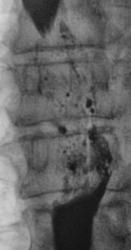

Линейные томограммы в боковой проекции

По представленным снимкам, у меня сложилось впечатление что пищевод как бы сдавлен извне (овал), возможно образованием в заднем средостении; при этом на довольно продолжительном участке есть нарушение архитектоники складок слизистой с множественными участками barium depletion (стрелки), свидетельствующими в пользу изъязвления.

Исходя из вышесказанного, по данному случаю: сдавление просвета и смещение пищевода мягкотканным образованием, выходяшим за пределы стенки, изъязвление передней стенки пищевода. Заключение: подслизистая опухоль пищевода с изъязвлением, вероятнее всего лейомиома. Рекомендации: эндоУЗИ с биопсией, КТ.

После проведенного рентгенологического исследования органов грудной полости - рентгенографии и томографии, при которой были выявлены увеличенные лимфатические узлы в корнях лёгких и средостении, было проведено рентгенотелевидение пищевода с прицельной рентгенографией и исследованием пищевода на трохоскопе, с контрастированием пищевода водной взвесью сернокислого бария "различной консистенции" - от сверхжидкого - до пастообразного, для "выяснения состояния" заднего средостения. Была зарегистрирована и документирована "локальная деформация пищевода" на протяжении 9,5 см. с перестройкой структуры "рельфа слизистой оболочки".